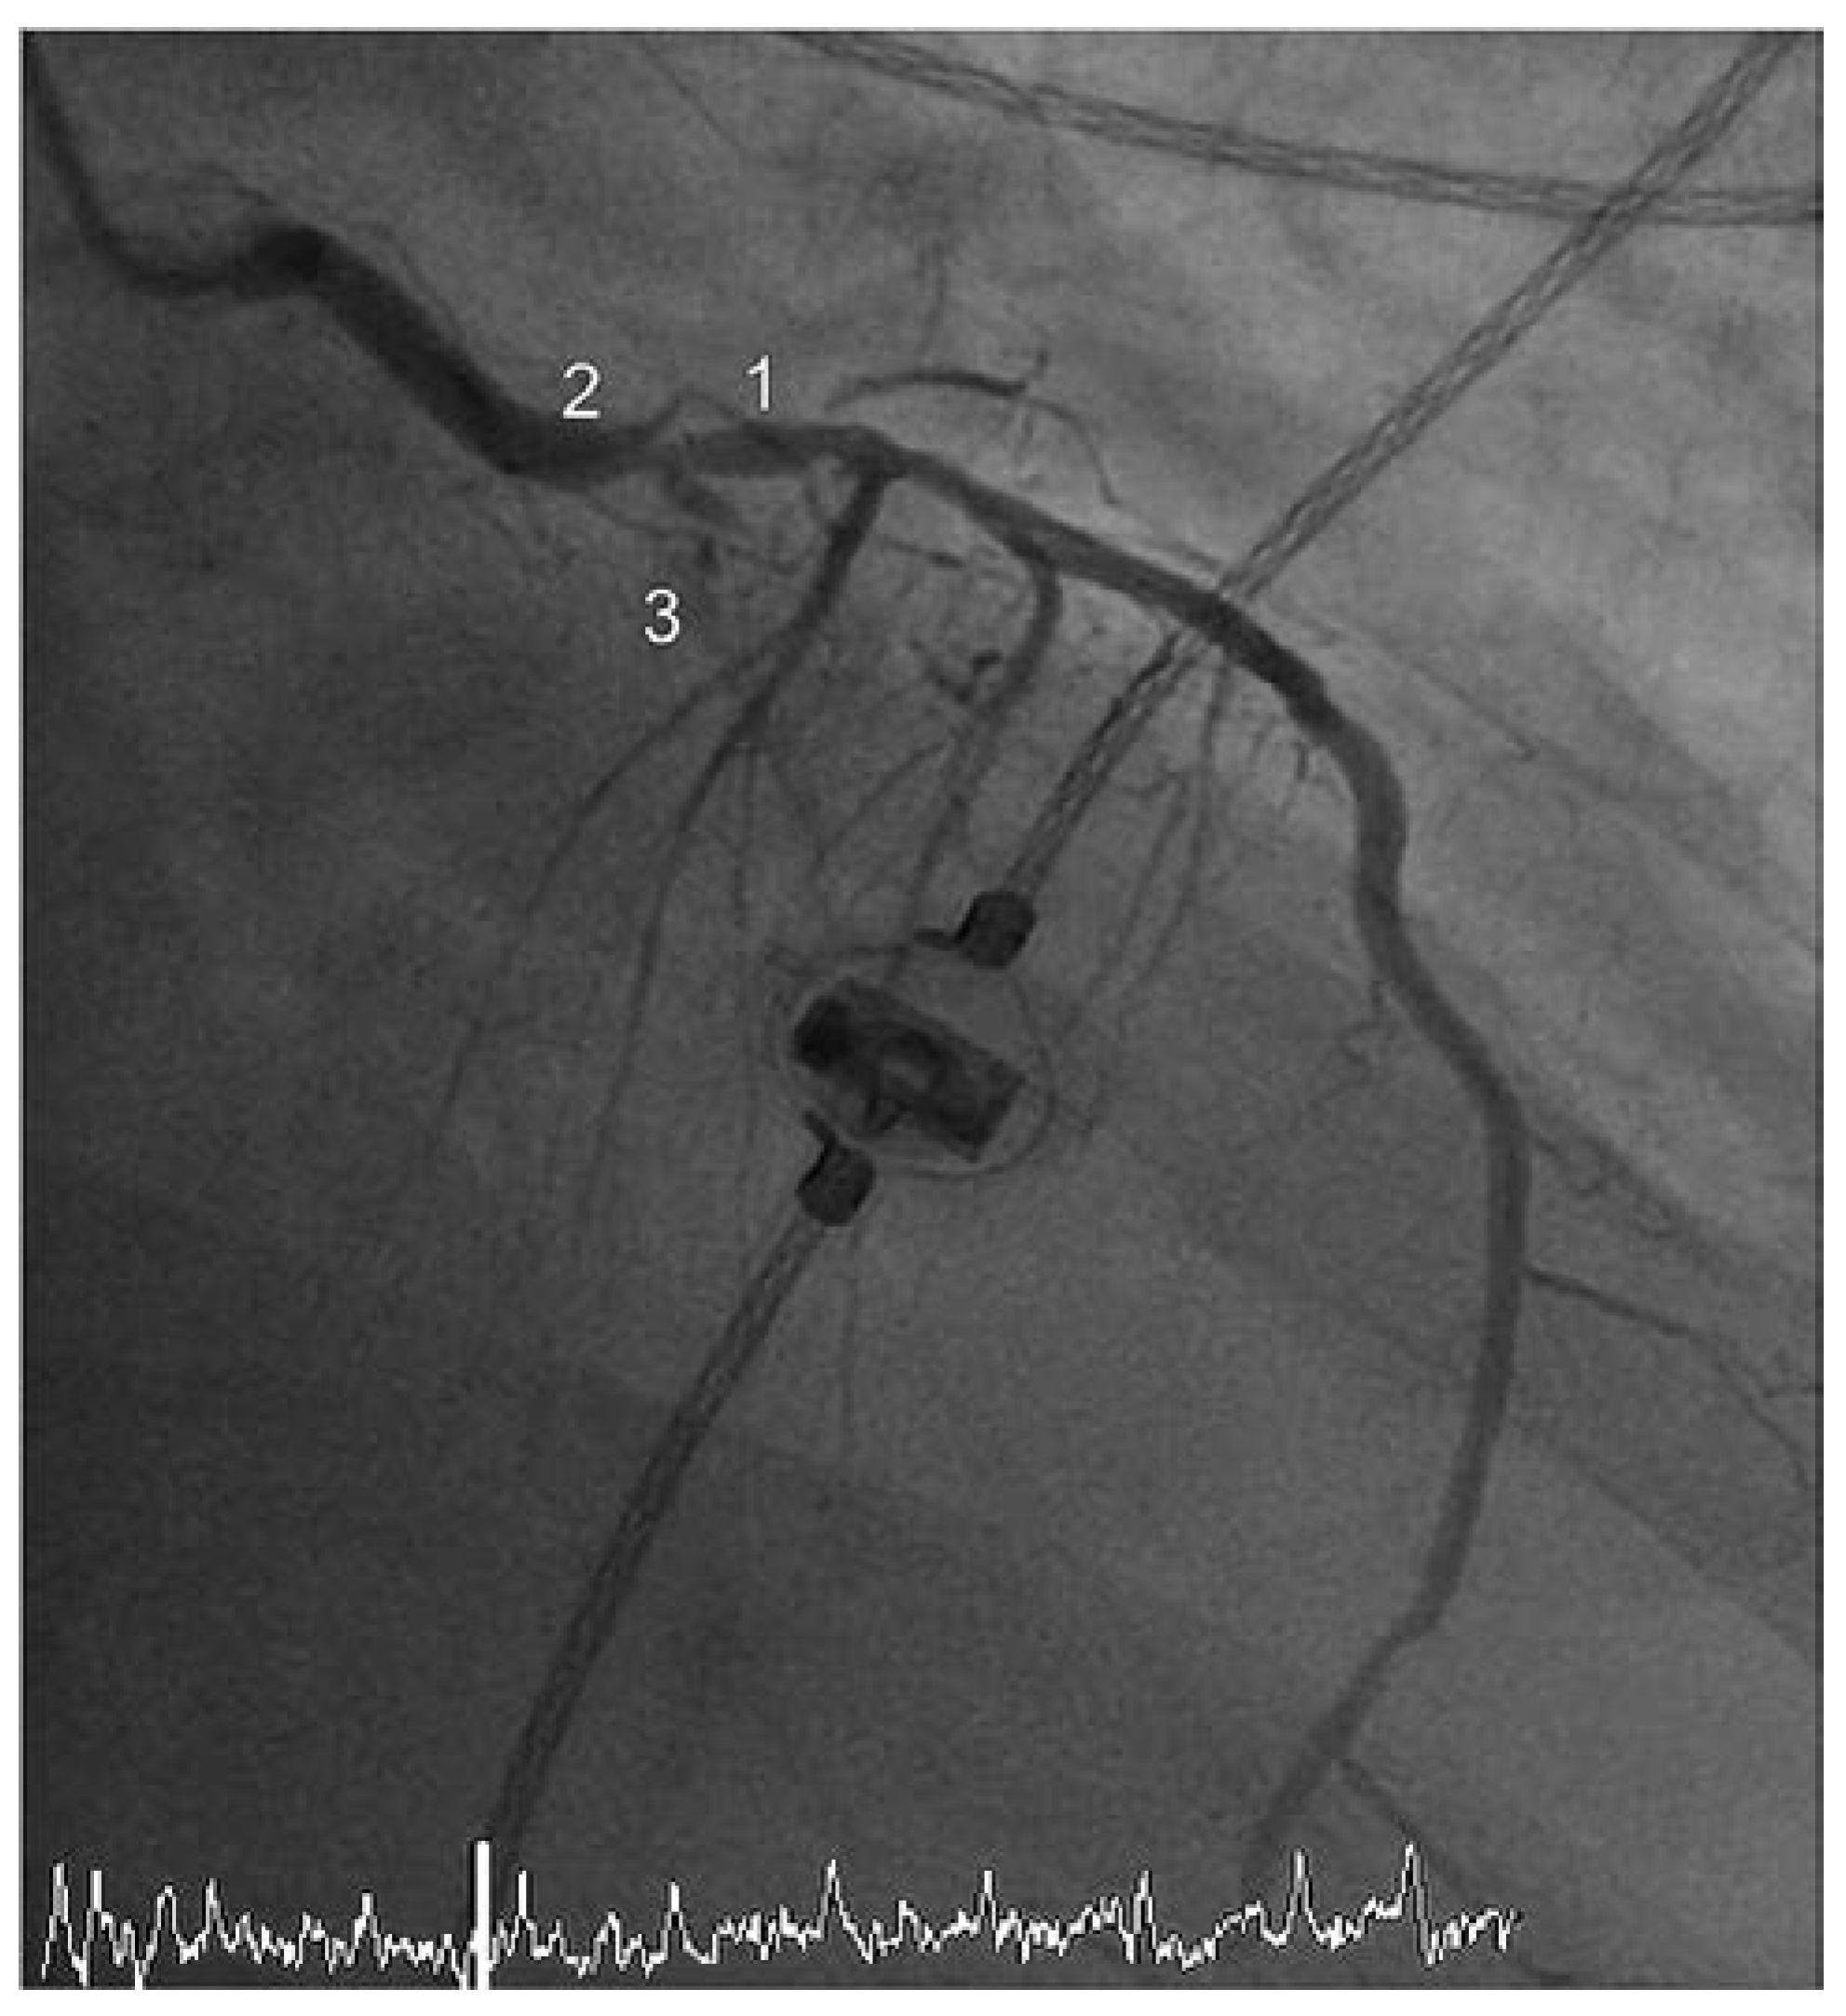

Die Zuweisung des 90-jährigen Patienten durch die Sanität erfolgte aufgrund eines akuten anterioren ST-Hebungsinfarktes mit typischer Symptomatik und zweifach über der Norm erhöhtem hoch-sensitivem Troponin T. Die Koronarangiographie zeigte als ursächliche Läsion einen Verschluss des mittleren Ramus interventricularis anterior (RIVA) (Abbildung 1). Insgesamt fand sich angiographisch eine schwerere koronare 3-Gefäss-Erkrankung: 70% Hauptstammstenose, mittlerer RIVA-Verschluss, subtotale Stenose des Ramus intermedius (RIM), 70% Stenose des 1. Marginalastes des Ramus circumflexus (RCX) und ein chronischer Verschluss der rechten Koronararterie (RCA). Ventrikulographisch zeigte sich eine schwer eingeschränkte linksventrikuläre systolische Funktion (Auswurffraktion [EF] = 25%) bei Akinesie der Vorderwand sowie Hypokinesie der übrigen definierten Segmente.

Abbildung 1. Koronarangiographie vor Intervention – Fall 1. 1 – RIVA, 2 – Hauptstamm, 3 – RIM, 4 – Marginalast 1/RCX. 5 – retrograde Darstellung der chronisch verschlossenen RCA.